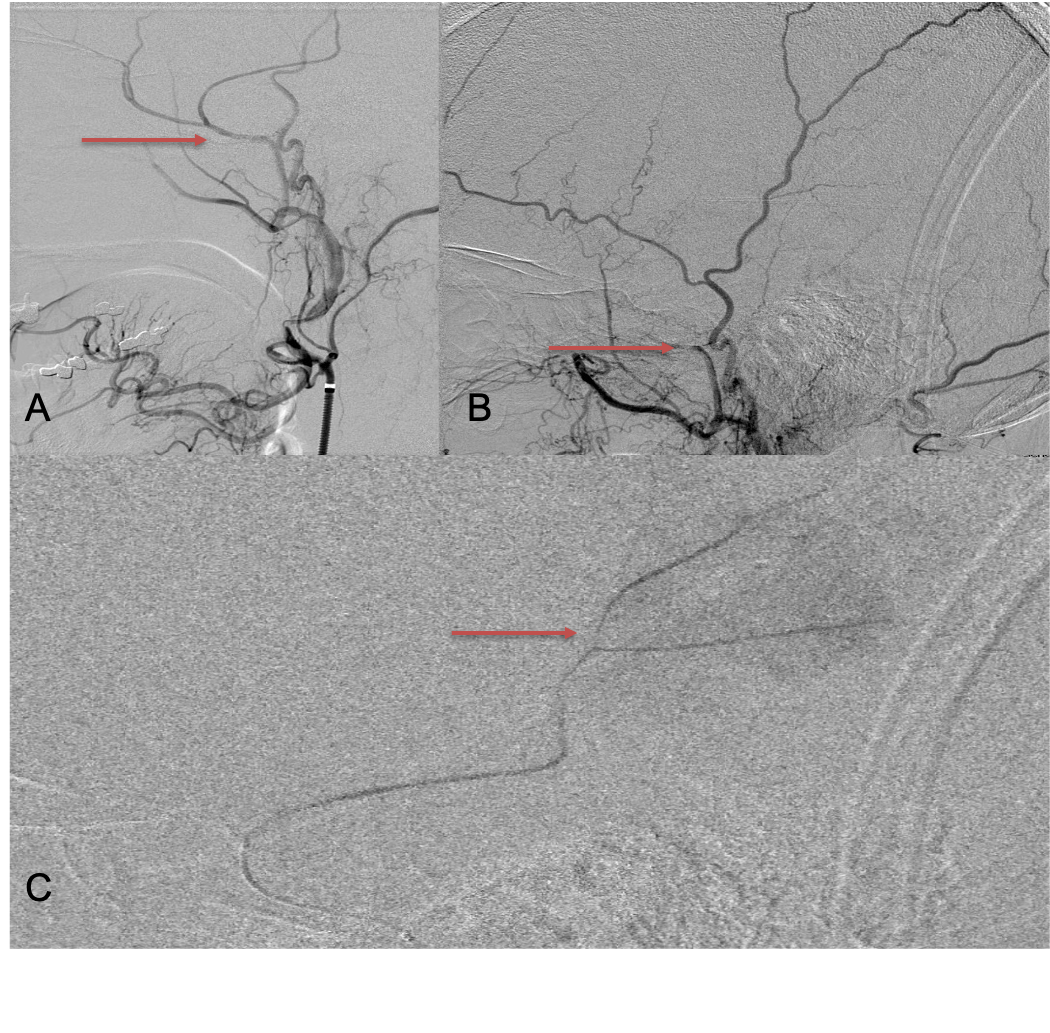

Figure 1. A) 6 weeks post mild trauma B) 4 weeks post mild trauma demonstrate stable subacute subdural collections with mild growth and sulcal effacement.

A man in his 80s developed mild dizziness and headache following incidental trauma working in his garage one day. He presented several weeks later to the ER and was diagnosed with bilateral subdural hematomas, which were initially managed with observation, low dose Decadron, considering the mildness of symptoms, advanced age, and history of CLL with thrombocyptopenia (<100k). Over the next 4 weeks, the collections remained relatively stable with evidence of slight growth (10 to 12 mm thickness, and 2 mm right to left shift) on NCT (Figure 1. A and B).